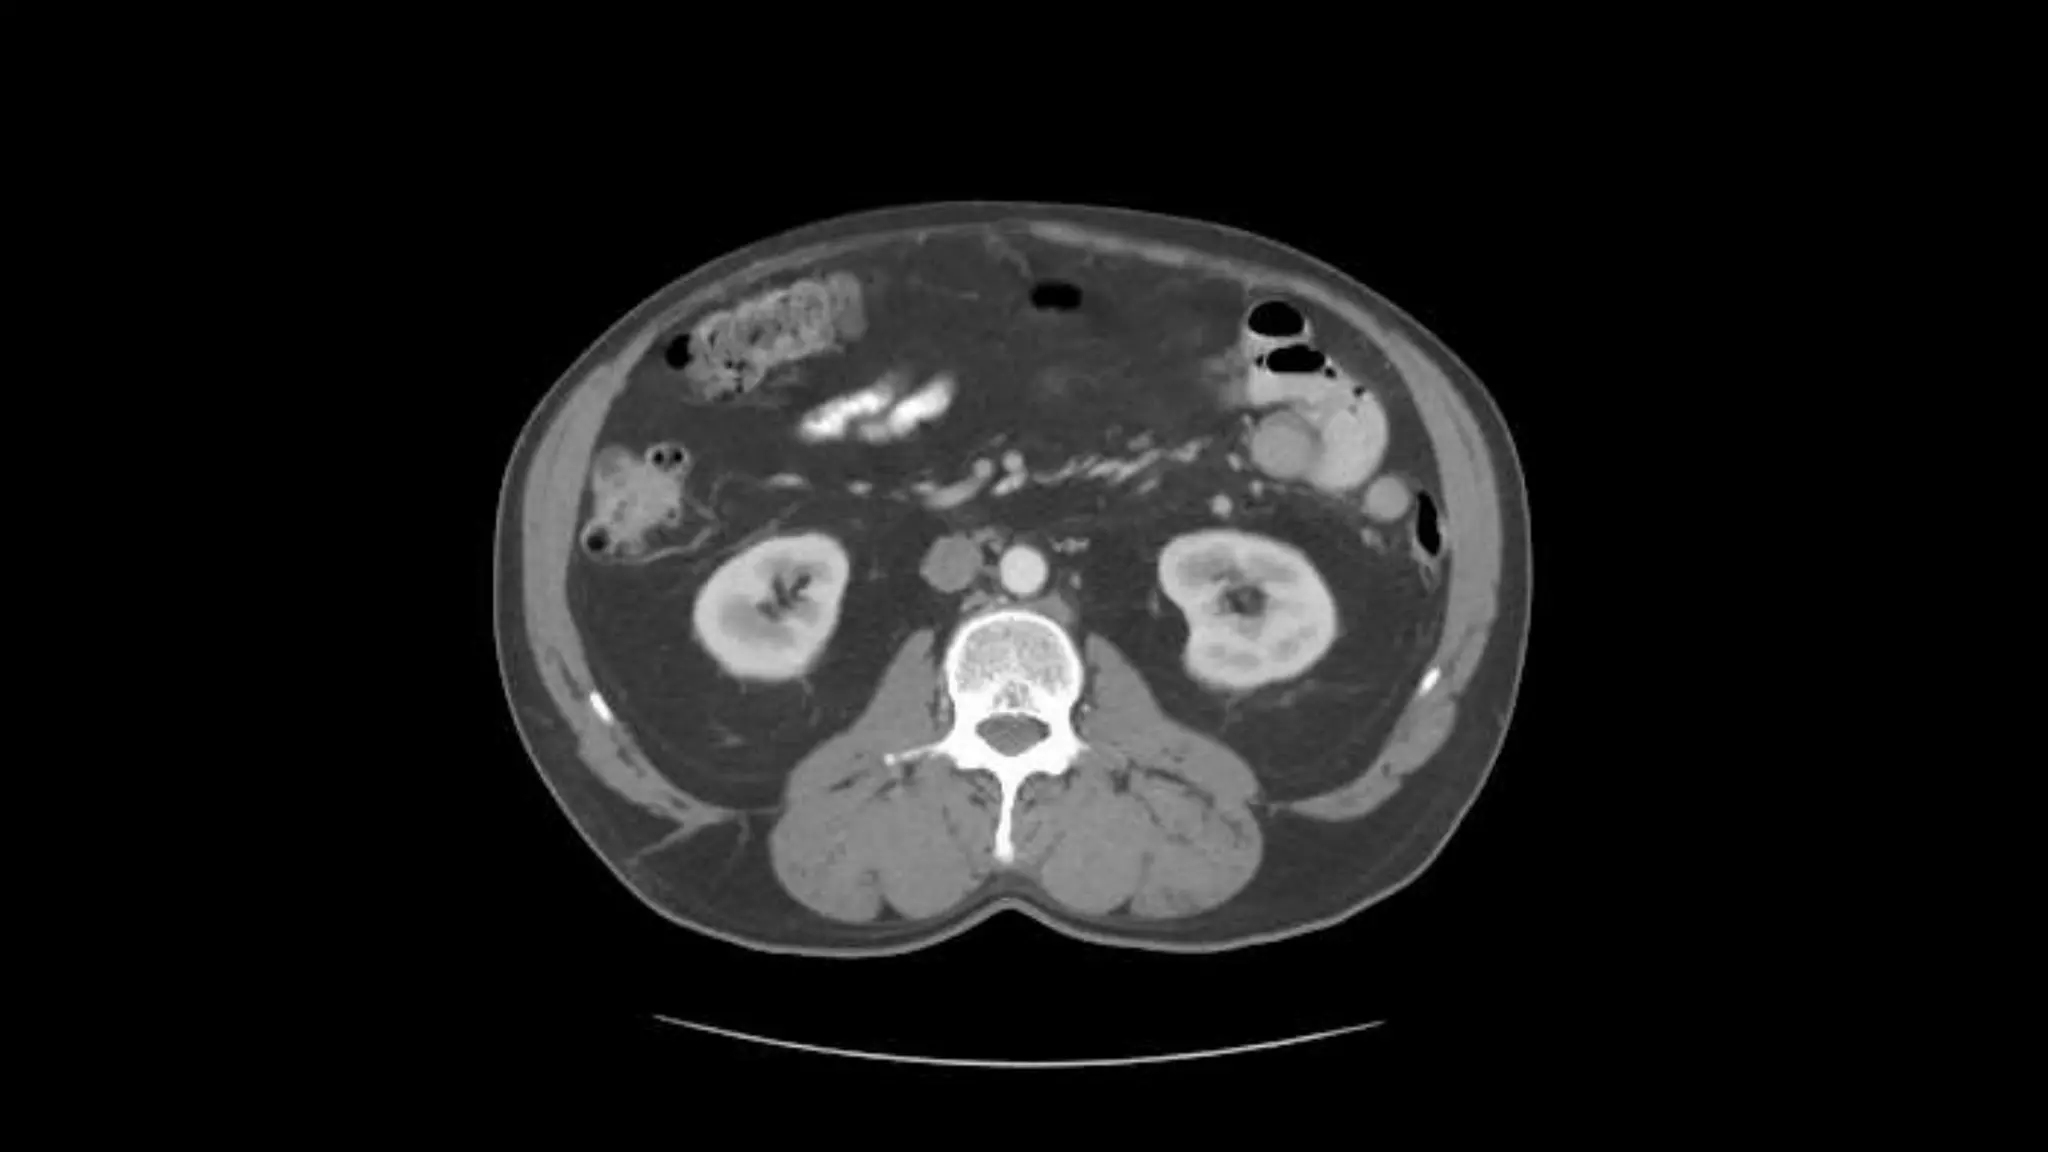

Renal Veins emptyinginto the IVC. We also see the right renal artery branching off the Aorta, follow it down till you see it enter the right kidney. The Superior Mesenteric Vein is outlined on the top of this image. If you follow the SMV up, you will see it empty into the Portal Vein.

Here we seethe right and left renal vein entering into the Inferior Vena Cava. We Also see the left renal artery branching off the aorta and heading toward the left kidney. Page up and down to trace these vessels.

Superior Mesenteric Vein– follow it up as it joins the Splenic Vein to form the Portal Vein